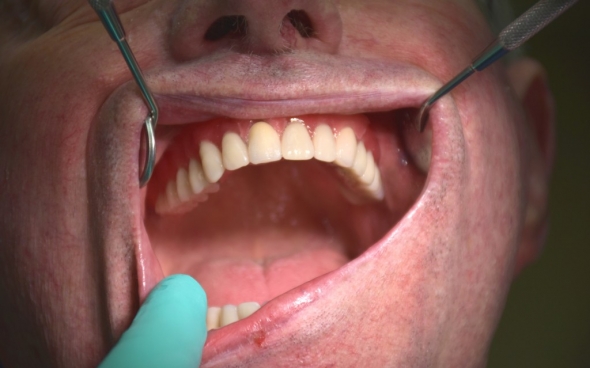

Metallkeramische Oberkiefer- und Unterkiefer-Vollbrücken

Der 48 jährige österreichische Patient erschien an unserer Zahnklinik zu einem Beratungstermin, wo eine Röntgenaufnahme und ein Kostenplan für metallkeramische Vollbrücken im Ober- und Unterkiefer mit insgesamt 25 Kronen erstellt wurden.